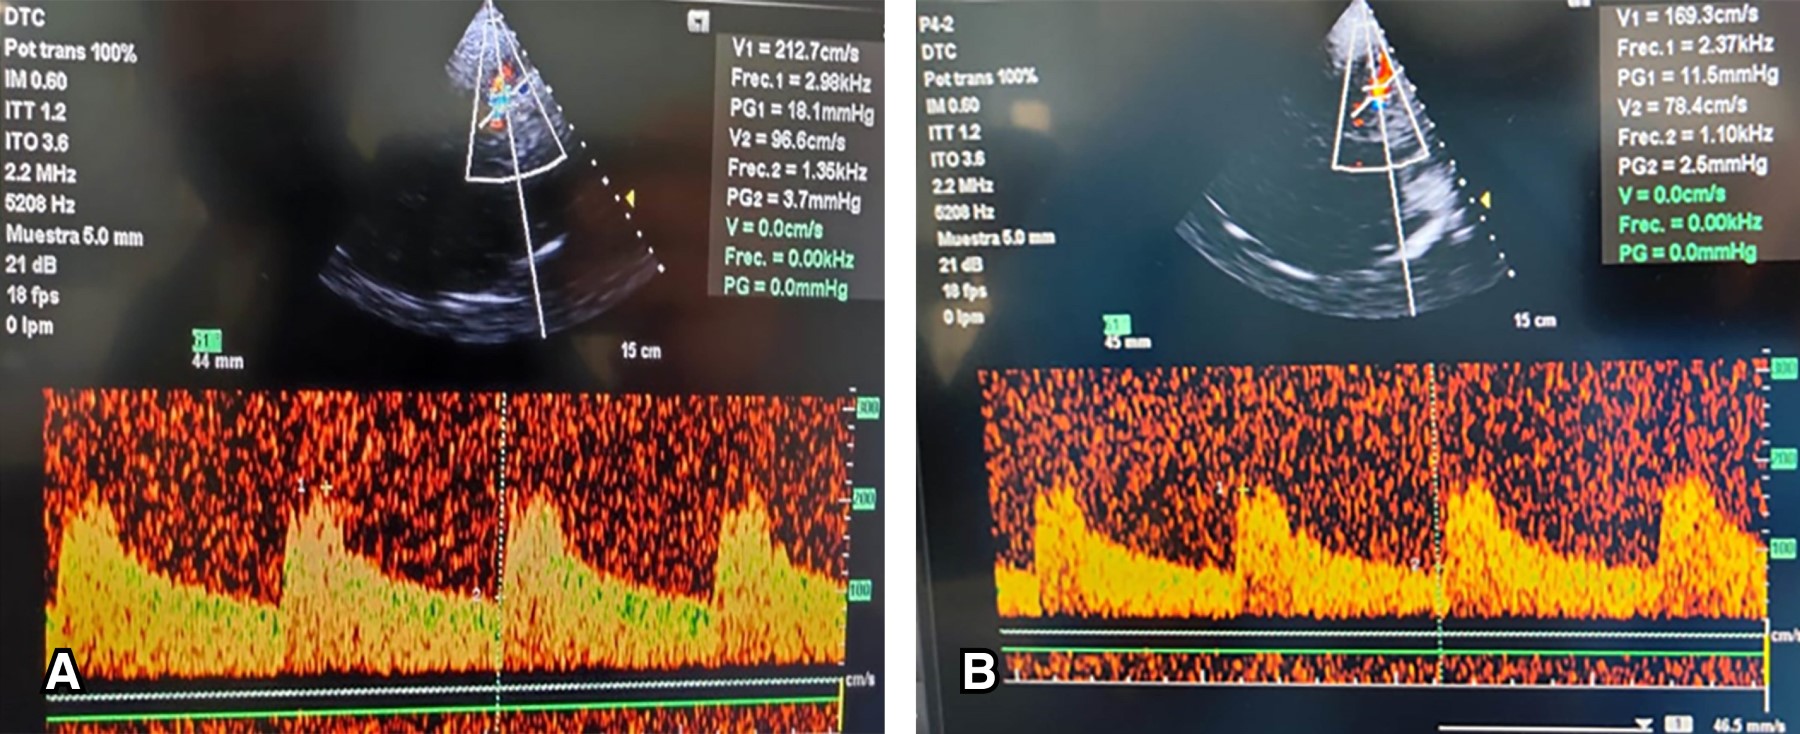

Además, como parte del protocolo diagnóstico, se realizó angiorresonancia cerebral, en la cual se evidenció la presencia de un hematoma fronto-basal derecho de 52.4 × 23.8 × 29.9 mm y un volumen estimado de 20 mililitros en fase aguda temprana con edema perilesional, sangrado subaracnoideo, espasmo de la arteria cerebral media de lado izquierdo y un aneurisma en la arteria comunicante anterior (Figura 2).

Figura 2